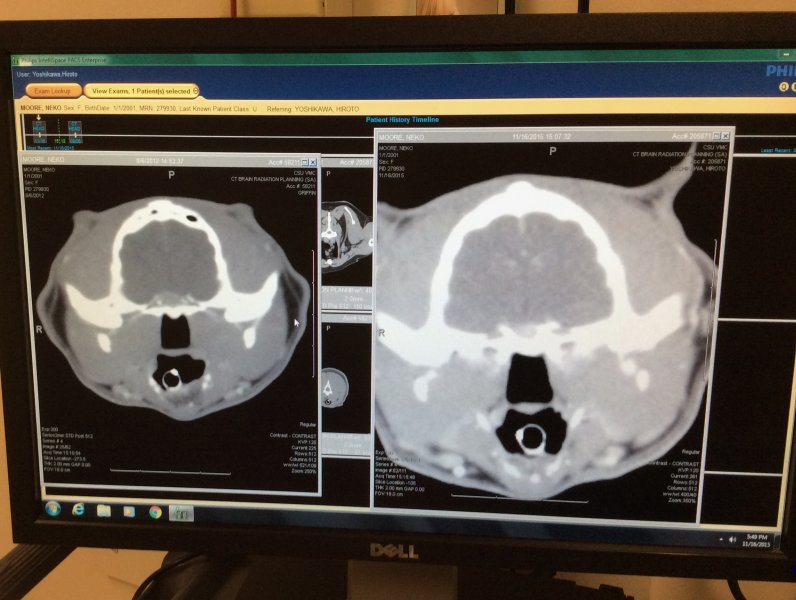

Talking with radiation oncologist re: the CT scan @ 9:00 am.

Sounds like I good result, I think? Did she say the tumour was smaller? Not sure what "really great" means. I've already said this before, but not sure I'd revisit treatment in six months. Poor boy has been through a lot and SRT can take 2-3 years to work, so six months is too soon. Plus I'm not sure another CT and anaesthesia with no news is what his body needs.